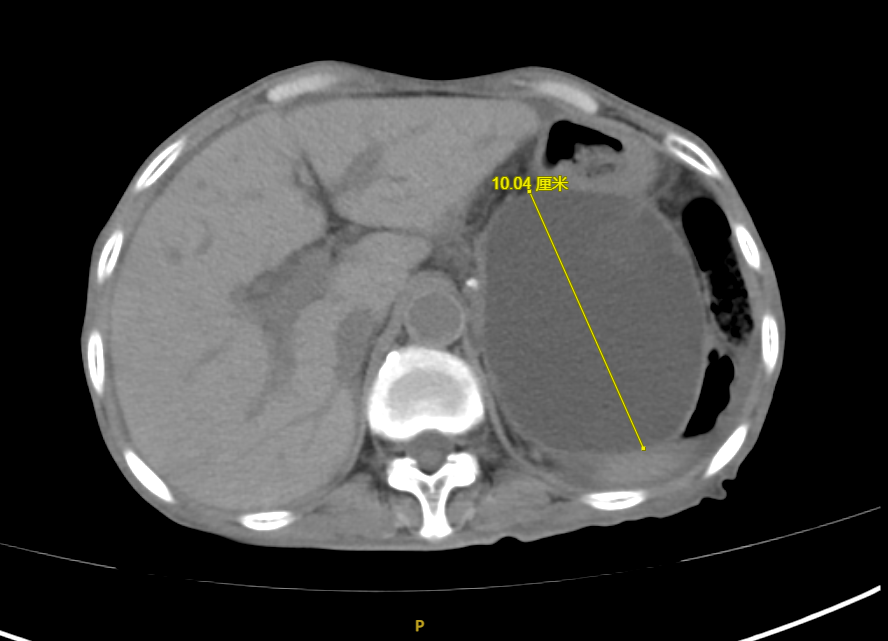

手术后

术后程女士腹痛、腹胀症状迅速得到了缓解,复查CT示囊肿较前显著缩小,目前已康复出院。